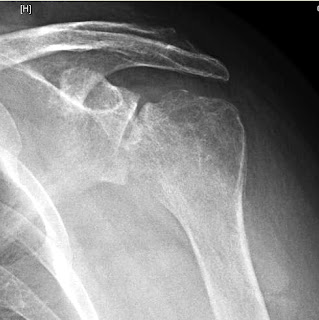

A year ago he had an injection into his shoulder, after which his shoulder pain increased dramatically. He then underwent an arthroscopic washout for a shoulder joint infection that he thinks may have been due to staphylococcus.

He then presented to us with a completely stiff shoulder and these x-rays.

We plan a debridement with cultures, a primary hemiarthroplasty and intravenous Vancomycin and Ceftriaxone.

Comment: We do not know the degree of sterile precautions that were taken at the time of his injection. In any event, this case demonstrates that shoulder injection is not without risk.